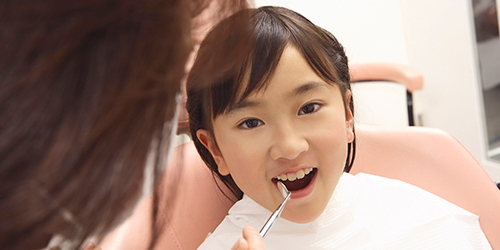

小児歯科

虫歯予防を中心とした治療を行っていきます。

ご両親とともに、お子様の健康な歯をつくりあげるお手伝いをいたします。